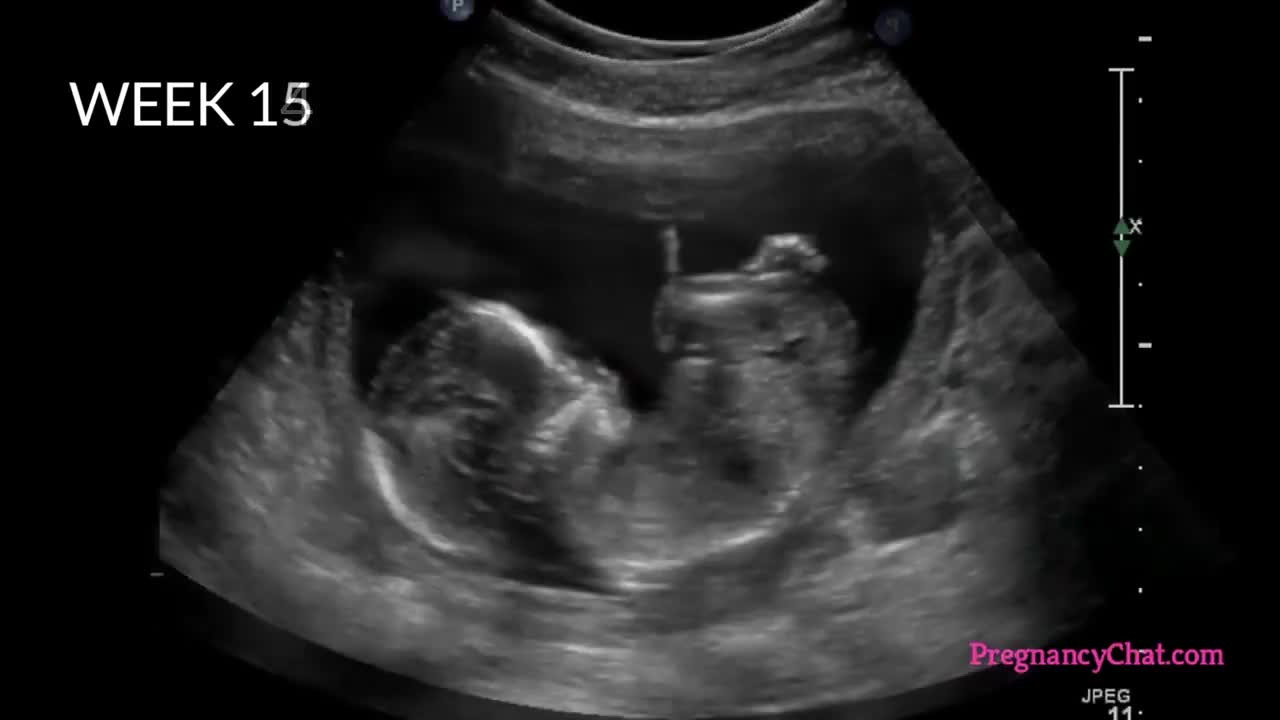

Tiến trình thai nhi lớn lên từ khi trứng gặp tinh trùng

Những tuần đầu trong bụng mẹ, thai nhi chưa tượng hình và được dưỡng chất từ cơ thể mẹ nuôi nấng, hoàn thiện các bộ phận.